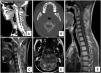

Presentamos el caso de un varón de 17 años que acude a urgencias por cervicalgia de 6 semanas de evolución, sin déficit neurológico. La tomografía y resonancia magnética mostraban una masa dependiente de C2 con infiltración de partes blandas e invasión del canal medular, sin signos de mielopatía. Se realizó biopsia guiada con tomografía. Esperando al resultado, el paciente desarrolló una tetraparesia aguda con incompetencia de esfínteres. Una nueva resonancia magnética mostró un aumento de la masa ósea tumoral con extensión epidural, mielopatía y nuevas lesiones vertebrales. Se realizó una resección posterior y descompresión medular de urgencia, con fijación occipito-cervical. La recuperación postoperatoria fue completa. La inmunohistoquímica reveló un sarcoma de Ewing. Se inició quimioterapia con respuesta parcial. El sarcoma de Ewing primario atlantoaxial es una entidad excepcional con mal pronóstico. Su tratamiento es multidisciplinar, incluyendo una resección total si es posible, lo cual supone un reto para el cirujano.

We report the case of a 17-year-old male presented to the emergency department with a six weeks history of neck pain and no neurogical deficit. Computed tomography and magnetic resonance imaging revealed an expansile lesion in the axis, with soft tissue and spinal cavity invasion, without mielopathy signs. Tomography-guided mass biopsy was taken. Waiting for histopathologic results, the pacient developed acute tetraparesis and sphincter incompetence. Magnetic resonance revealed that the bone mass had grown with epidural compromise, mielopathy and new vertebral lesions. Medular decompression with laminectomy, excision of the posterior elements of axis with the involved soft tissue mass and occipito-cervical fixation was performed. Neurological recovery was complete. Inmunochemistry revealed an Ewing Sarcoma. Chemoteraphy treatment was given, with partial response. Primary Ewing sarcoma of atlas-axis is a rare entity with poor prognosis. Multidisciplinary approach treatment is needed, with a total surgical resection if it is possible, a real challenge for the surgeon.